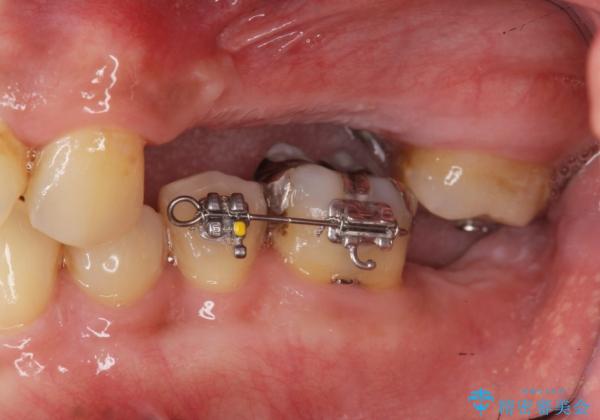

・対合歯の欠損による歯の挺出→マイクロインプラントを用いた小矯正を行うことで咬合平面を是正

噛み合う歯が欠損し長時間放置すると、歯が挺出(歯が伸びてくる)し欠損補綴を行おうにもスペースが足りない場合があります。(クリアランスの不足)

加えて咬合平面の乱れを放置したまま無理やり補綴治療を行うと、特定の部位に過大な力がかかり当該歯を痛めてしまうこともよくあります。